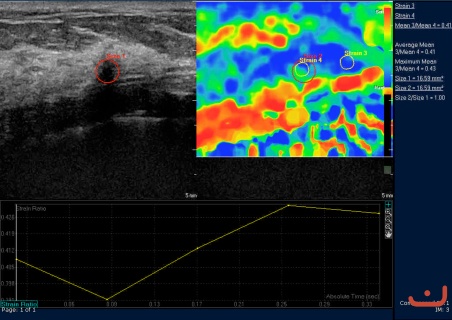

Case 55-E1

Benign solid mass

Friday, 22 May 2015

141.49 KB (452 x 320 px)